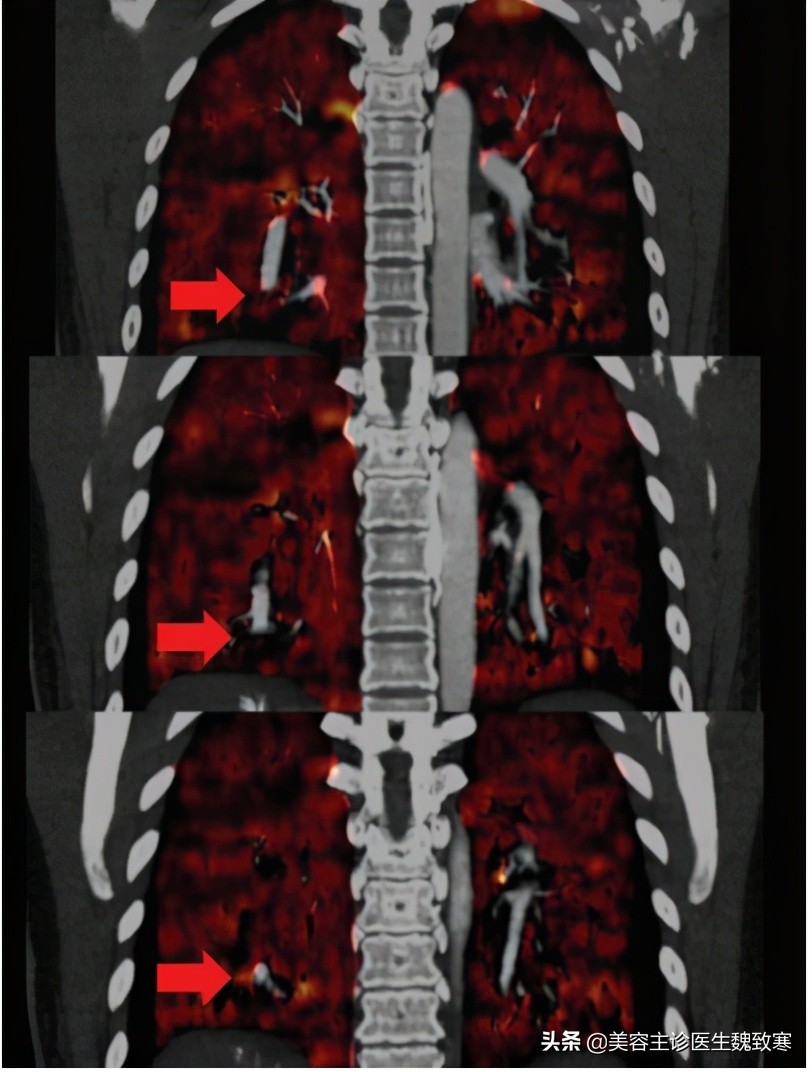

图4

随后,

应用去甲肾上腺素、特利加压素和多巴酚丁胺维持她的血压和心脏强度。患者还接受了激素、低分子肝素、呼吸支持、酸碱补充、抗感染药物、内环境维护、胃保护和器官功能支持等治疗。虽然给予了积极的治疗,但患者的循环衰竭逐渐恶化,升压药剂量的不断增加使维持稳定的情况变得复杂。在第一次心脏骤停期间(入院后7小时),患者在复苏后短暂恢复自主心率。在发生第二次心脏骤停(格拉斯哥昏迷评分:3分)后,立即按压胸部,反复注射肾上腺素和阿托品,静脉注射碳酸氢钠纠正酸中毒,并增加升压药泵的剂量。经过2个小时的抢救,重症监护室的医生宣布患者死亡。死者家属拒绝了尸检。